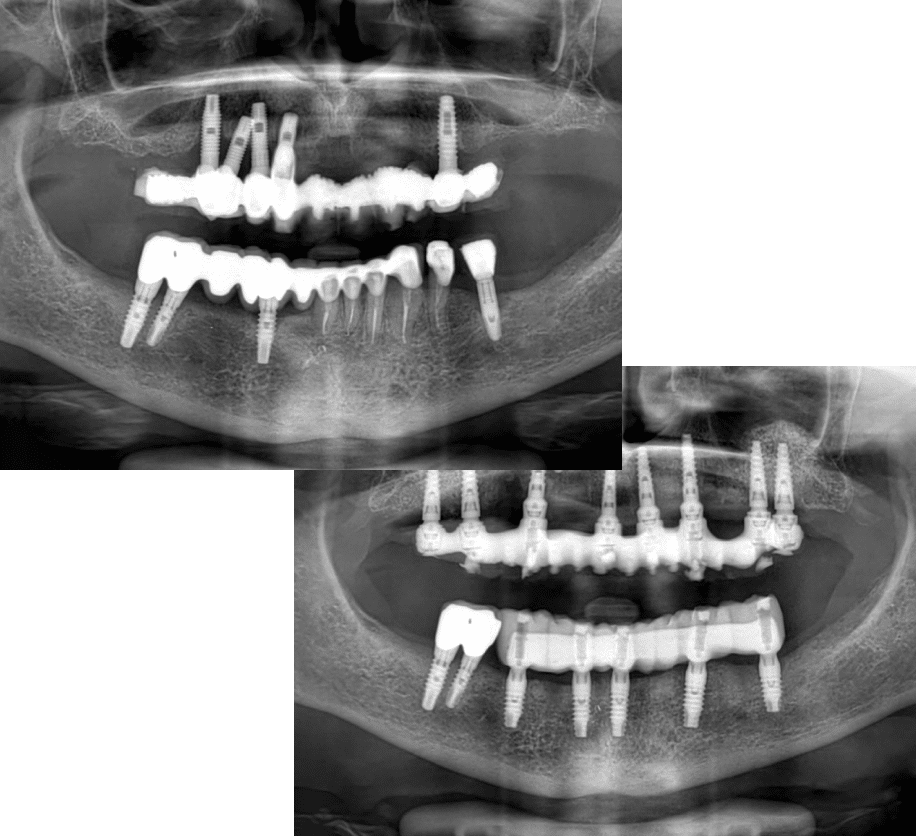

Descrizione del caso

La paziente si è presentata con problemi infettivi a livello di entrambe le arcate. Ascessi ricorrenti, sintomatologia cronica e infiltrazioni cariose hanno reso necessaria una riabilitazione con terapia impianto-protesica.

Abbiamo realizzato due grandi rialzi del seno mascellare per creare le giuste condizioni ossee. Dopo avvenuta rigenerazione, abbiamo eseguito un impianto a carico immediato.